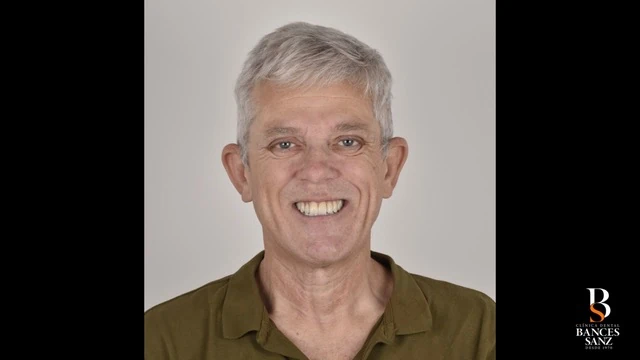

- Diseñar una sonrisa acorde al rostro del paciente.

- Mejorar de forma notable la estética de la sonrisa.

- Ganar en confianza y bienestar en su día a día.